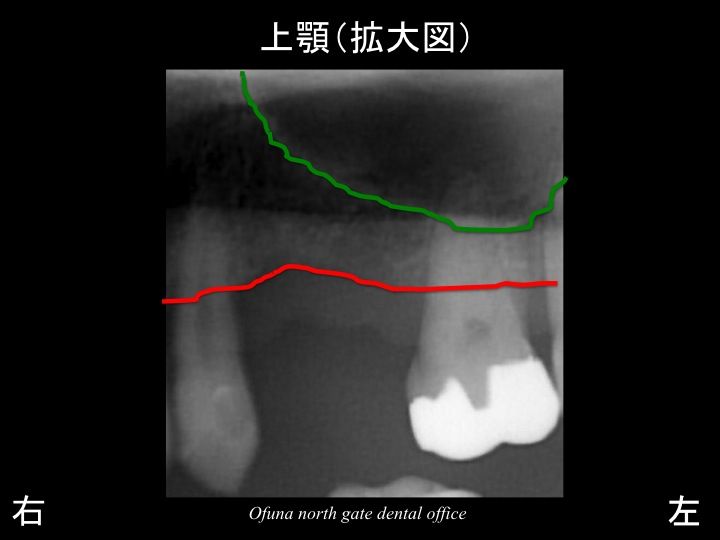

骨吸収が非常に大きかったのです。

いつものように 骨吸収の状態を分かりやすくするために

骨吸収の状態を線で書いたのが以下のレントゲンになります。

青線が骨吸収を起こす前の骨の位置です。

赤線は、現在の骨の位置です。

次に上顎洞です。

以下の緑線は上顎洞という空洞です。

緑線の内側は空洞なのです。

骨ではありません。

ただの 穴 です。

上顎左側の欠損部を拡大して見てみましょう!

拡大したレントゲンが以下です。

骨の高さがほとんどないのが分かるかと思います。